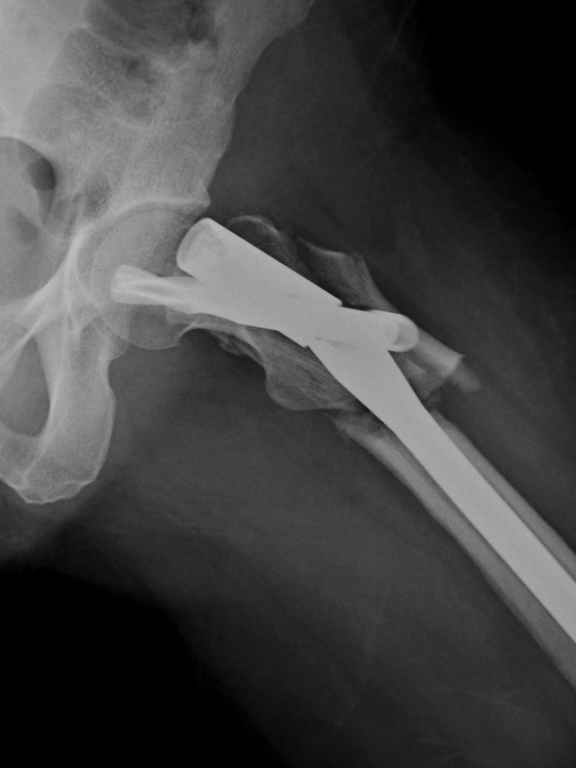

I was wondering if you could give me your thoughts on a case. 50 yo female with breast cancer who had pathologic fracture of proximal femur. Originally fixed with PFN which has broken.

Tough case. It should have healed, I think it was the right implant.

Was it in varus to start? Too much stripping w/ the reduction?; or poor protoplasm and cancer. On the lateral it looks like the piriformis starting point was reamed w/ starting point too posterior and aiming too ant. and med. This is a common problem w/ this fx and the proximal piece ends up

flexed, ER and in varus. This may have contributed to failure, but this deformity will be the same challenge on the revision. Do you have